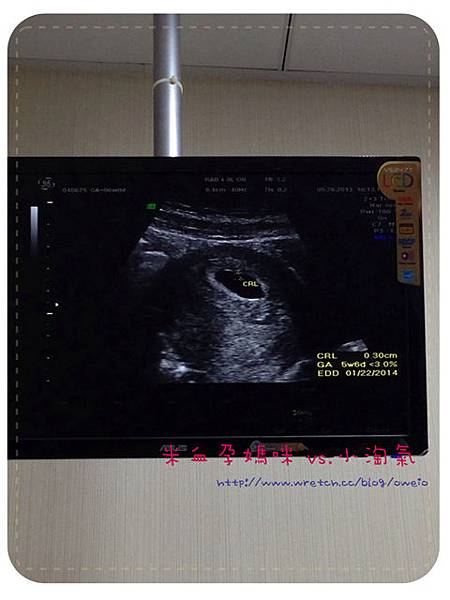

(照片中標註CRL的部份就是小淘氣的小心跳唷!其實還有更清楚的畫面,但我沒捕捉到

)

將。將。將。將。小淘氣的預產日是2014。01。22。左右唷